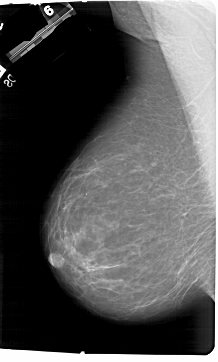

A_1177_1.LEFT_MLO

LEFT_MLO LINES 6871 PIXELS_PER_LINE 4126 BITS_PER_PIXEL 12 RESOLUTION 43.5 NON_OVERLAY